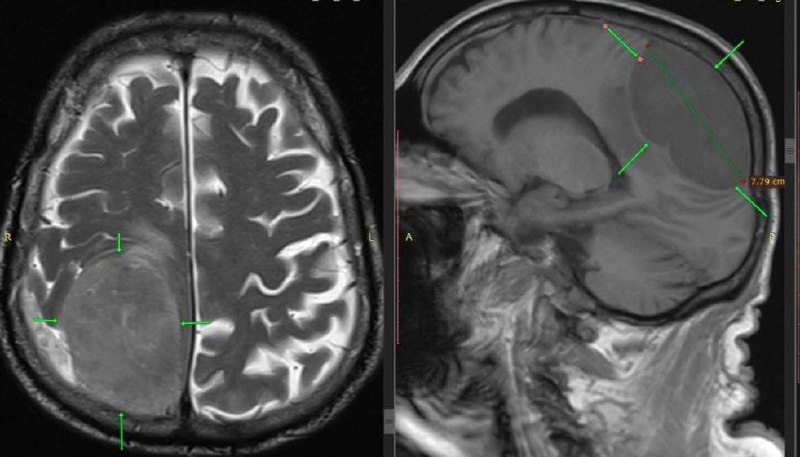

Мужчину доставили с симптомами инсульта: не двигалась левая половина тела. Но обследование показало другое — гигантское новообразование в зоне мозга, отвечающей за движение.

Нейрохирурги провели сложнейшую операцию и полностью удалили опухоль. Несмотря на высокий риск и возраст пациента, вмешательство прошло успешно.

Мозг восстановился, движения вернулись, опухоль оказалась доброкачественной. Мужчина уверенно идёт на поправку.

Фото: ГКБ Пятигорска.